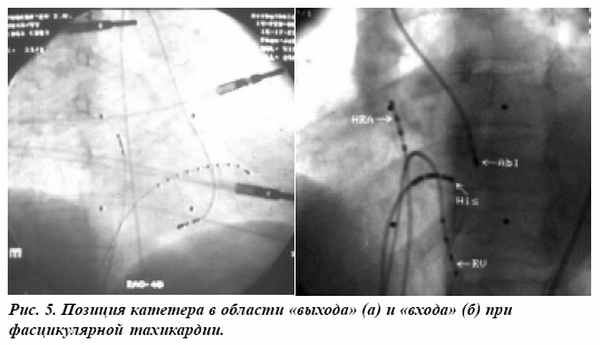

Критерии эффективности и направленность высокочастотного (ВЧ) воздействия изменялись с накоплением опыта операций. У первого из пациентов верификация зоны цепи re-entry на основании регистрации электрограммы волокон Пуркинье (рис. 3) привела к купированию тахикардии при ВЧ воздействии, однако на третьи сутки наблюдался рецидив.

При повторной операции электрод был смещен в область разветвления левой ножки пучка Гиса, что привело к стойкому устранению ЖТ. При выполнении последующих операций мы отказались от попыток регистрации потенциала волокна Пуркинье или средне-диастолических потенциалов. Область «выхода» определялась с использованием стимуляционного картирования (рис. 4, 5а).

При неэффективности ВЧ воздействий в этой зоне и сохранении индукции тахикардии, воздействие направлялось на проксимальную часть цепи re-entry, в область «входа», с использованием рентген-анатомических и ЭКГ (рис. 56) признаков.